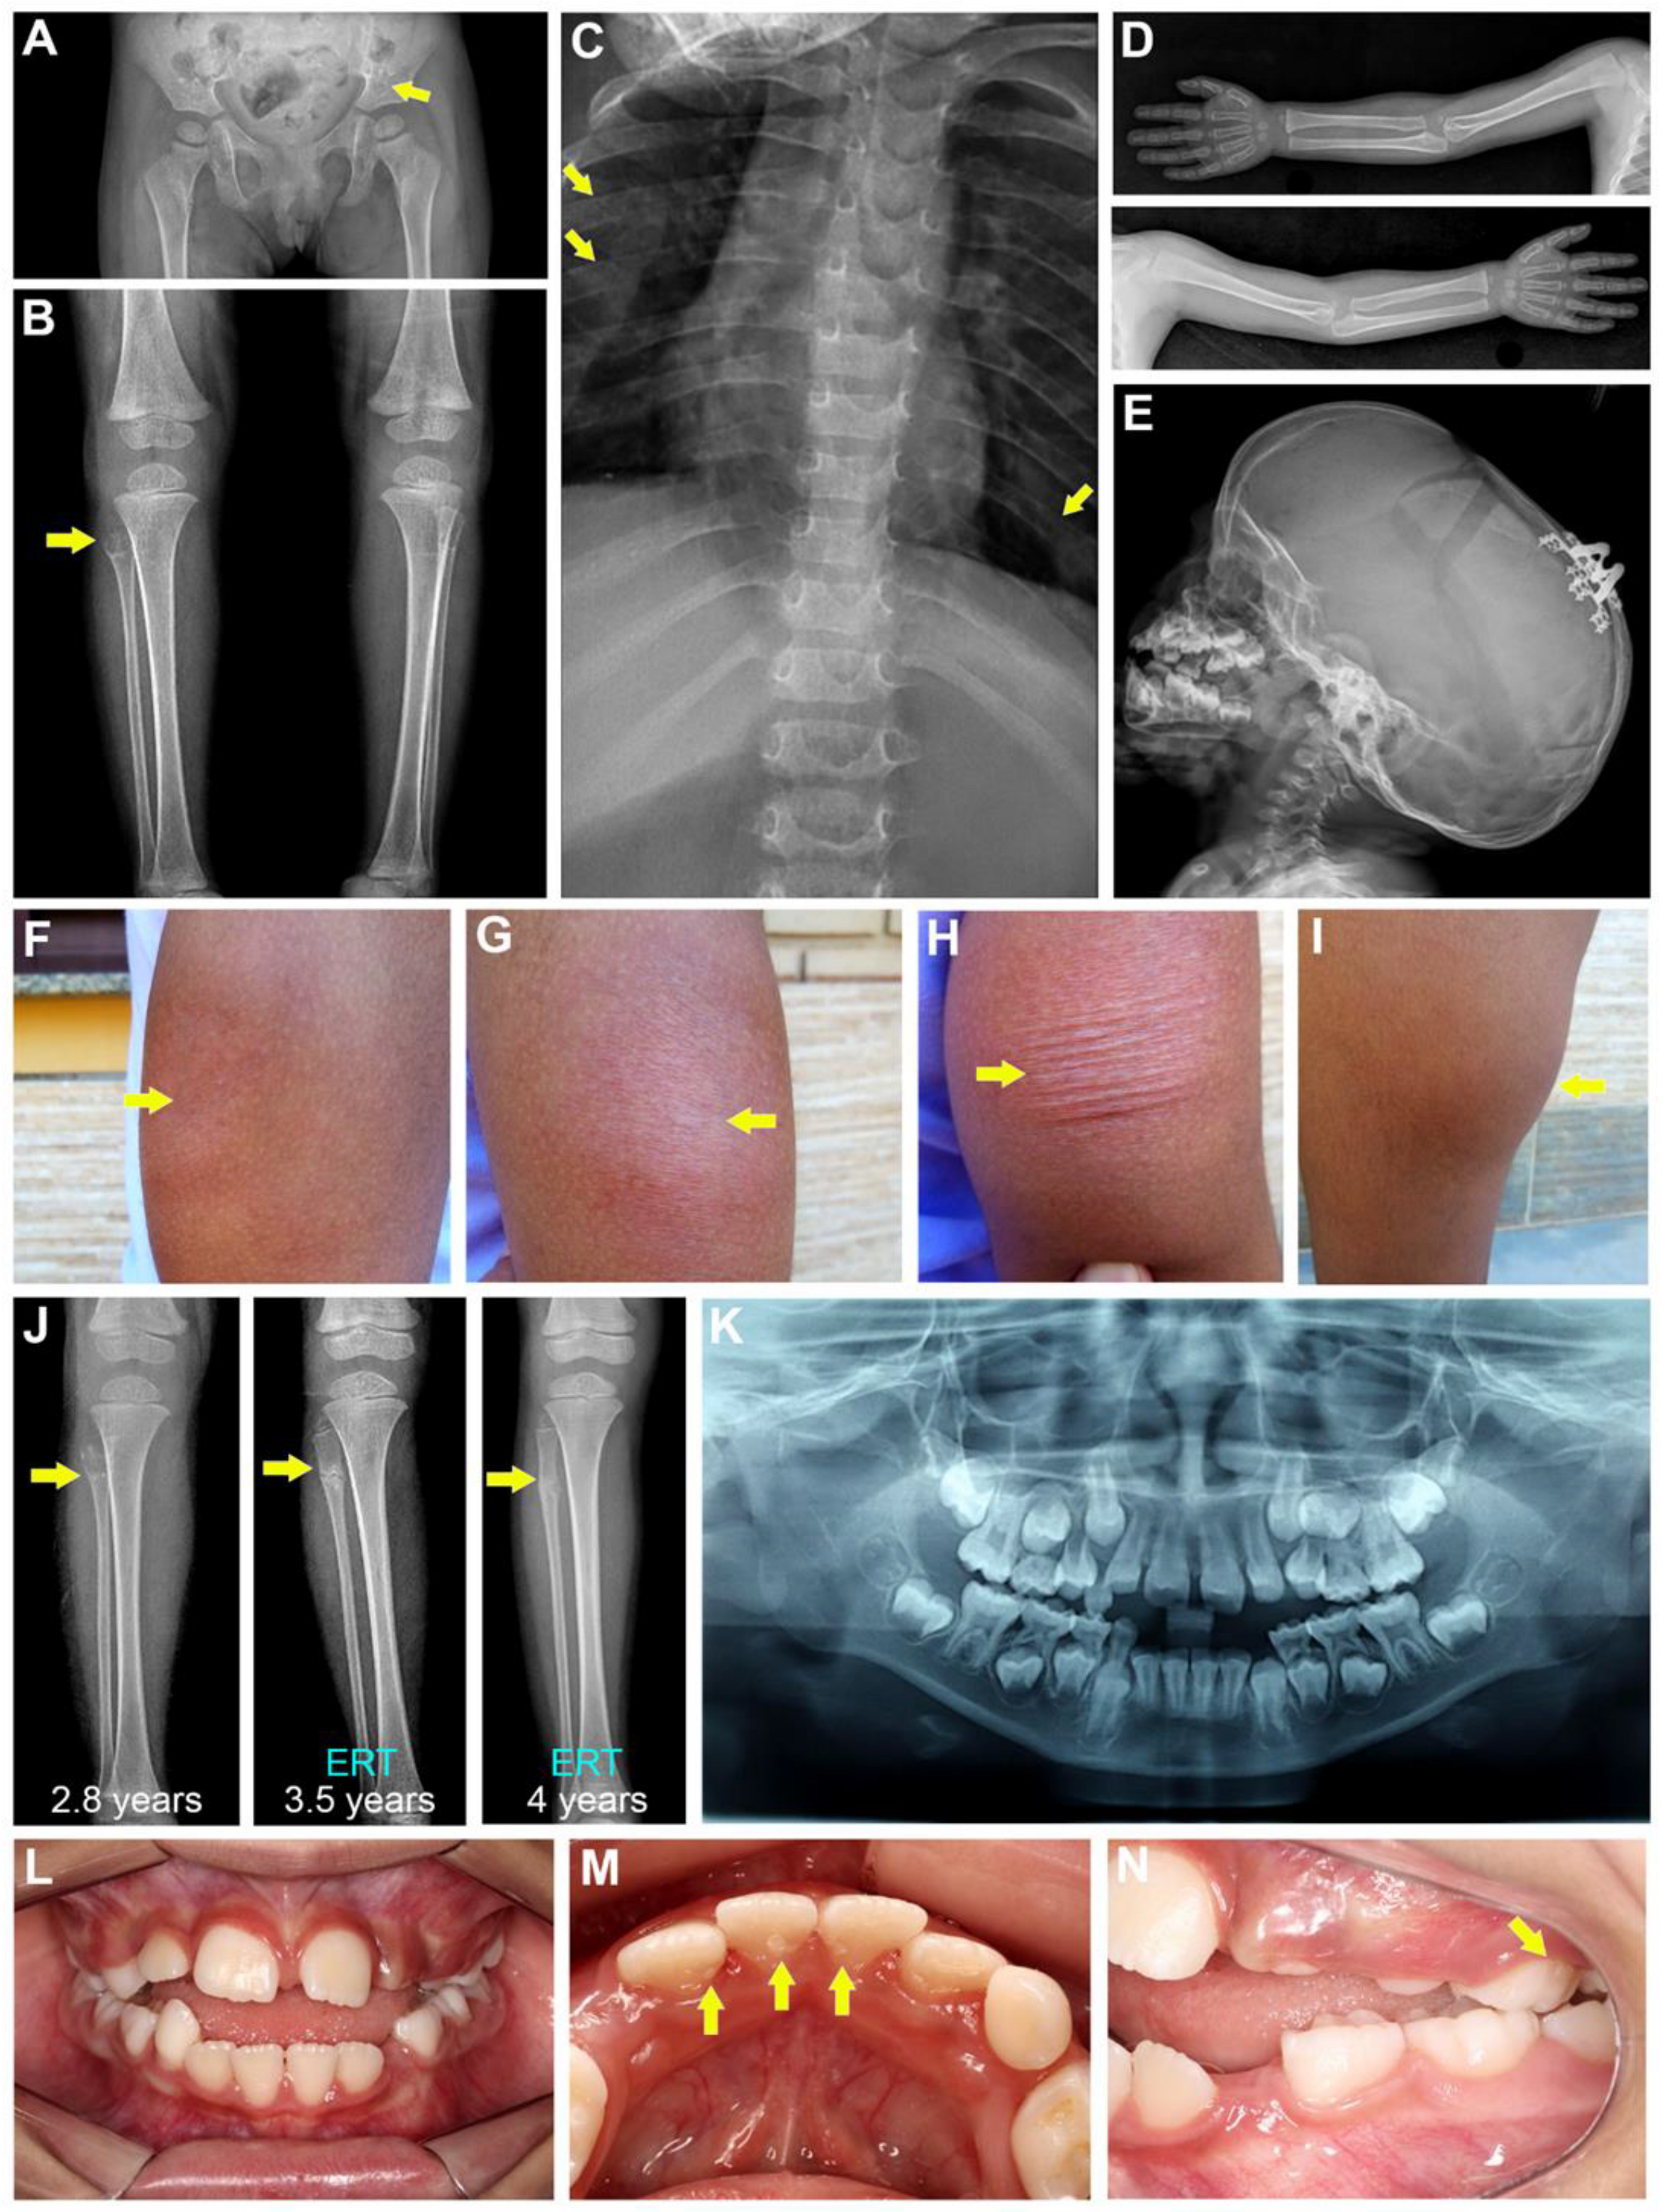

3.1. Medical and Dental History

3.2. Genetic and Pedigree Analysis